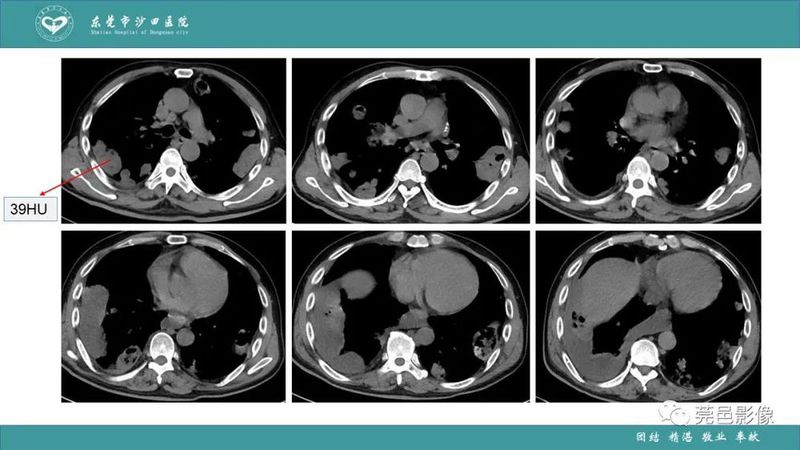

「肺炎克雷伯杆菌肺炎」影像学诊断+鉴别诊断